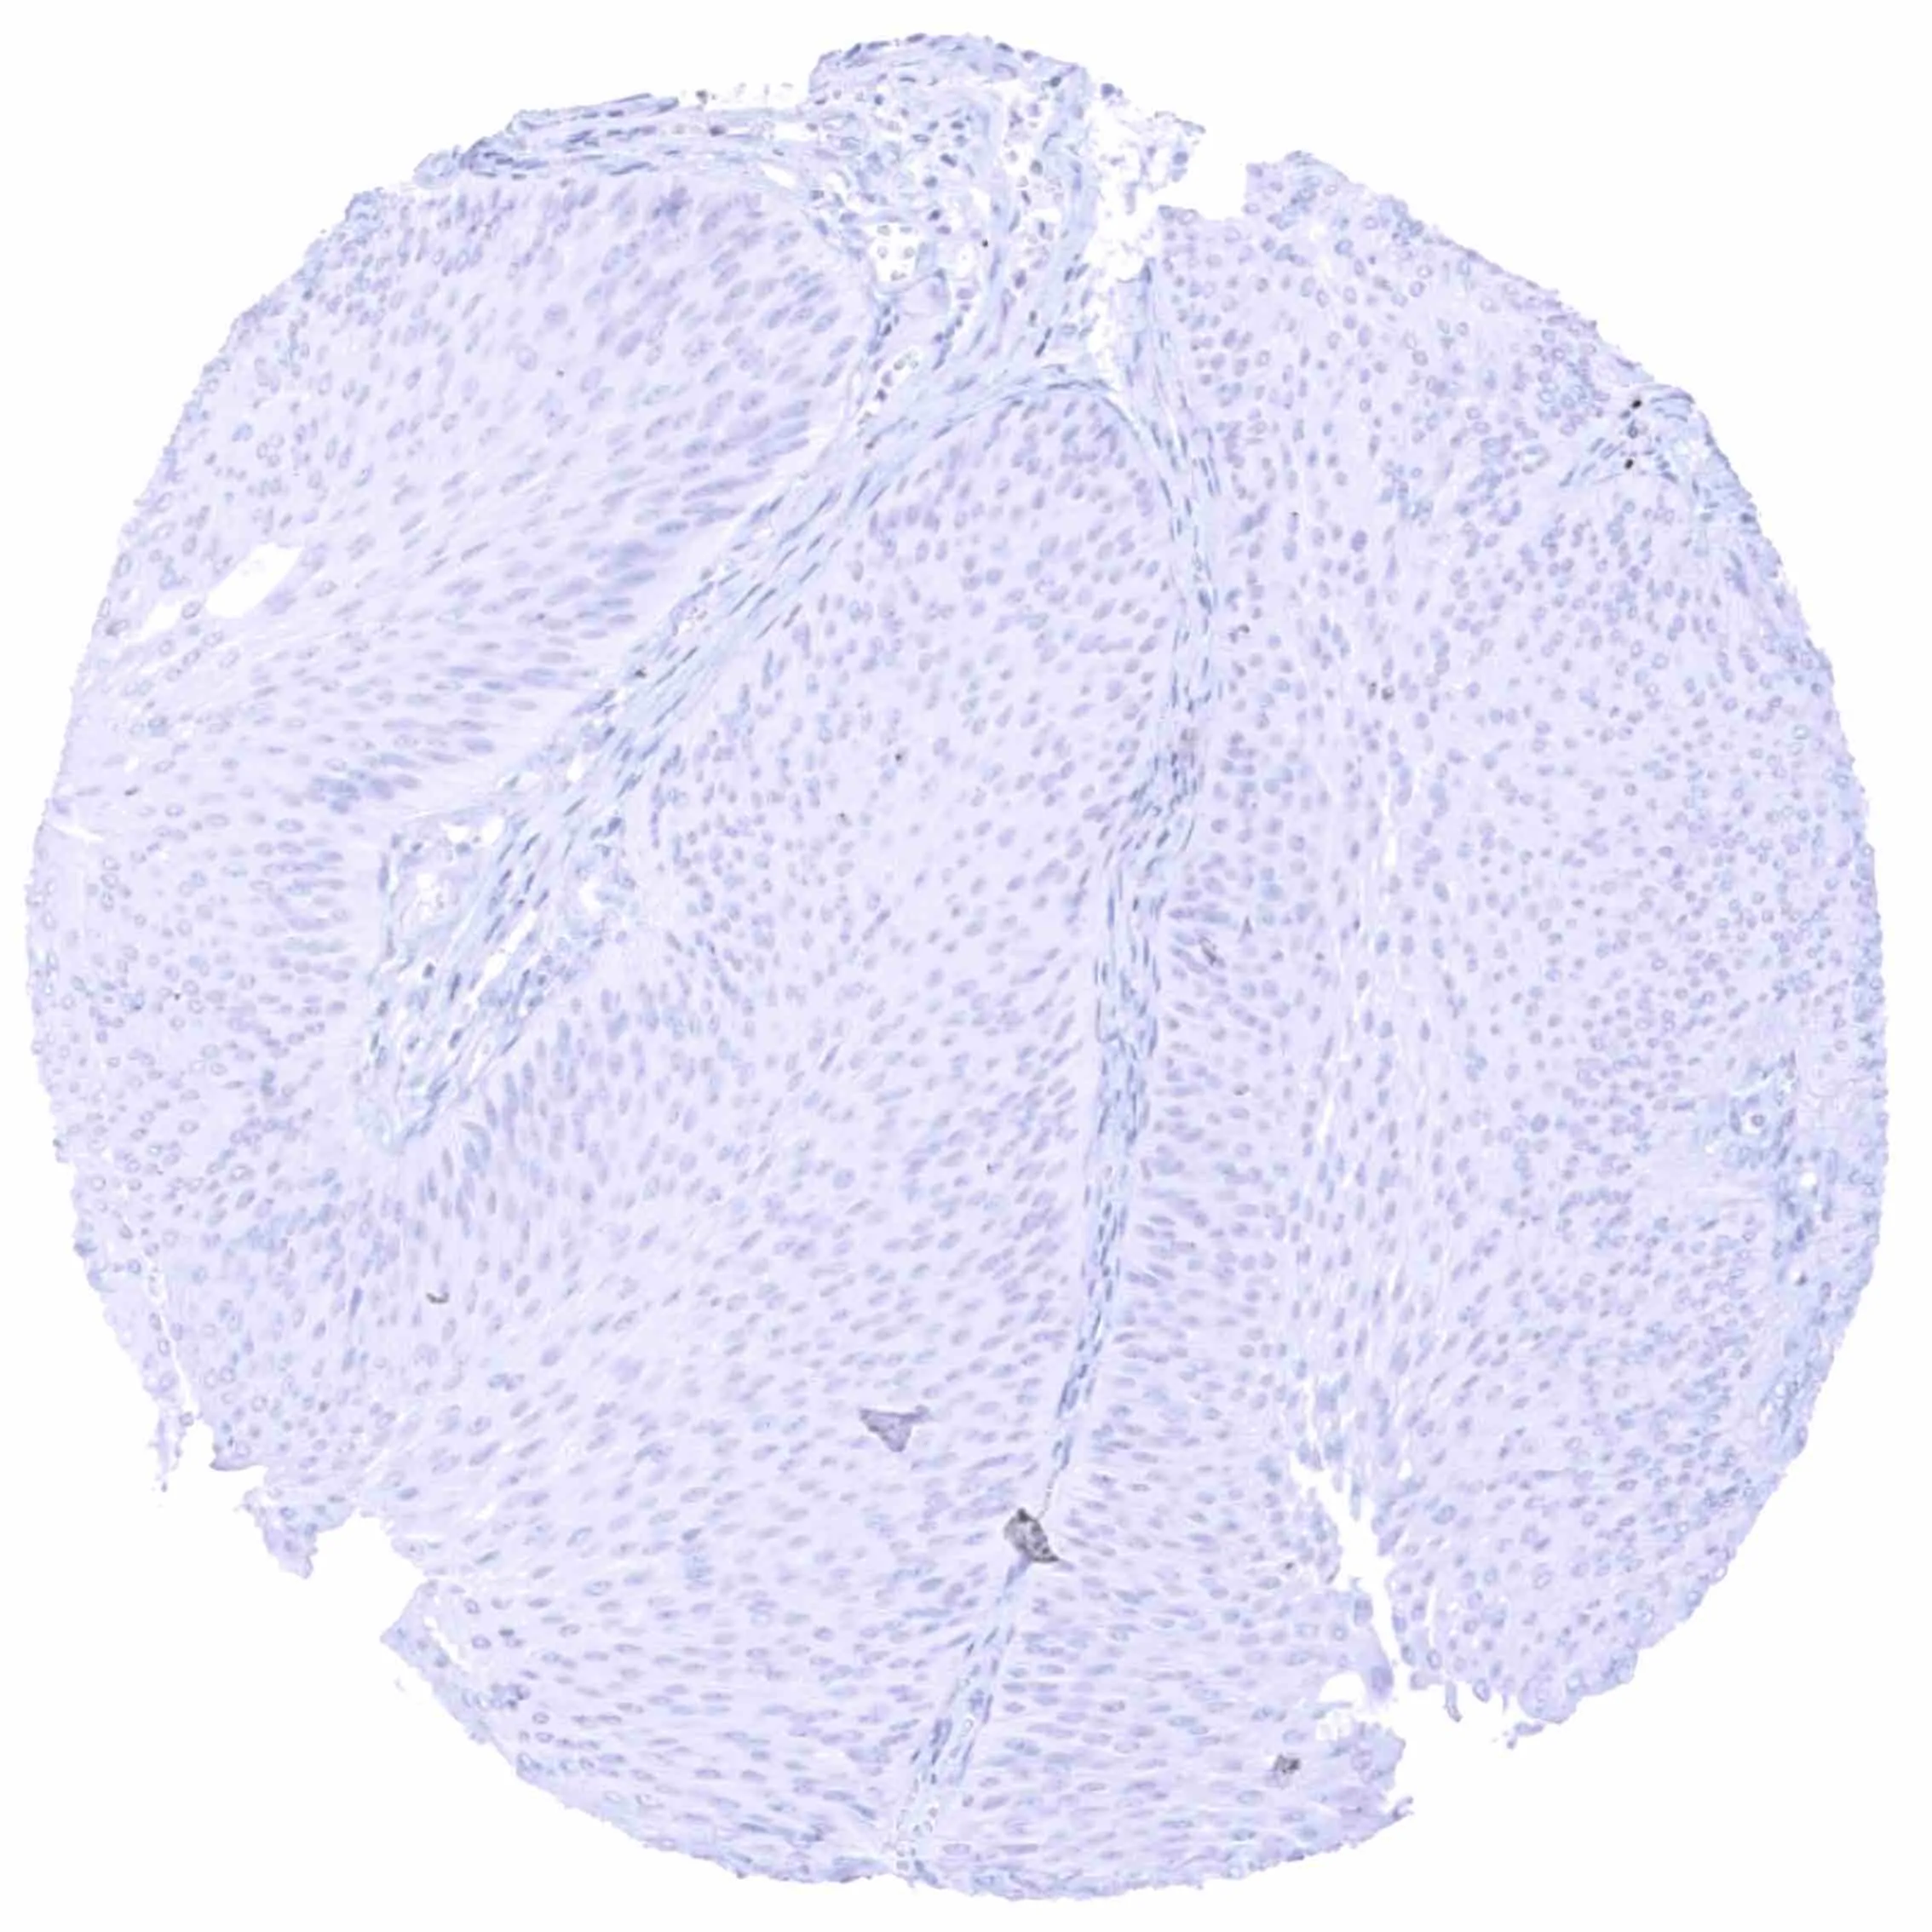

Oral cavity – EGFRvIII negative squamous cell carcinoma (low grade).

Oral cavity – EGFRvIII negative squamous cell carcinoma.